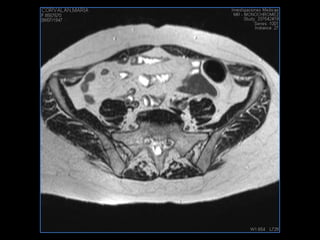

PROTOCOLO pelvis SAG T2, Y FAT SAT (FINOS) AXIAL T1  AX FAT SAT CON   GADOLINIO :  AX T1 Y COR T1 SAT: NO  FASE: RL THK: 3MM  COIL:  GAP: (FACTOR 1.4) 1MM FOV: 40 CM NEX:2 SINCRONIZACION RESPIRATORIA EN 3 O 4 CICLOS ALE

resonancia de abdomen